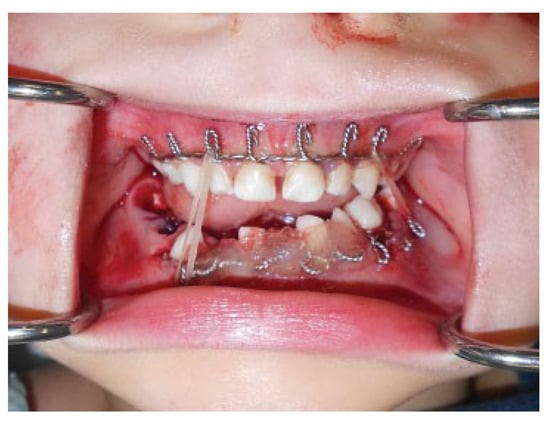

Modifications to this procedure include using 24-gauge stainless steel wire that is passed from the last molar as originally described (Figure 2). The wire is then twisted from one side of the dental arch to the other (Figure 3). Ideally, circumdental ligatures are passed to secure the individual teeth as the cable is being twisted (Figure 4). This will allow for secure fastening of the cable and ligature complex. Finally, when the wires composing the Risdon cable have reached the contralateral molar tooth, it is then secured and the final circumdental ligature is placed. The circumdental wires are cut and twisted in a traditional fashion that will allow loops for securing elastics or wiring to establish MMF or guiding functions (Figure 5). If elastics are used for MMF, it is most unusual for the Risdon wiring to pull off or otherwise fail as the elastics “give.” Aside from establishing MMF, this procedure may also be used for splinting avulsed or luxated teeth, and may be supplemented with autopolymerizing resin for stability (Figure 6). Following application of the Risdon cable, open reduction internal fixation may then be performed with the patient in MMF (Figure 7).

Figure 7. Open reduction internal fixation completed with intermaxillary fixation accomplished using rubber bands and Risdon cables.